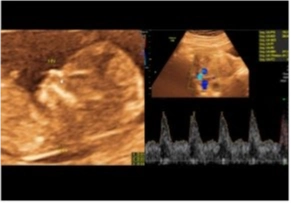

Doppler de Embarazo

11-13+6 / 22-24 / 30-34 Semanas

Para qué sirve la Ecografía Doppler

Sirve para medir flujos internos de las arterias uterinas y con ello medir riesgos hipertensivos en la madre, además de buscar en ciertas semanas marcadores de riesgos cromosómicos como síndrome de down, turner, etc.